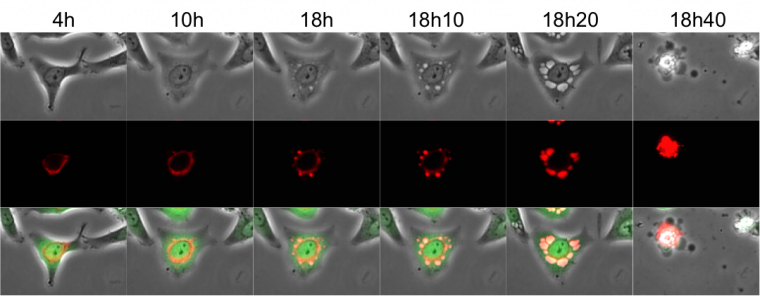

Nous avons ensuite voulu caractériser ces vacuoles formées dans les cellules infectées. En nous basant sur nos précédentes observations, nous nous sommes demandés si les vacuoles provenaient du RE. Nous avons donc filmé de nouveau les cellules infectées mais cette fois nous avons utilisé un marqueur du RE apparaissant alors en rouge (protéine fluorescente basée sur la calréticuline, qui est une protéine du RE – Figure 8). Nous avons observé que le signal rouge du RE se situait autour du noyau dans les cellules saines comme attendu mais que celui-ci s’intensifiait et migrait à l’intérieur des vacuoles. Cela a confirmé notre hypothèse : les vacuoles induites par le virus Zika se forment à partir du RE. Ce type de mort cellulaire montrant des vacuoles provenant du RE se nomme « la paraptose ».

Des cellules épithéliales (coloration verte) ont été infectées par le virus Zika et filmées par vidéo-microscopie pendant 20 heures. Le réticulum endoplasmique apparaît en rouge.